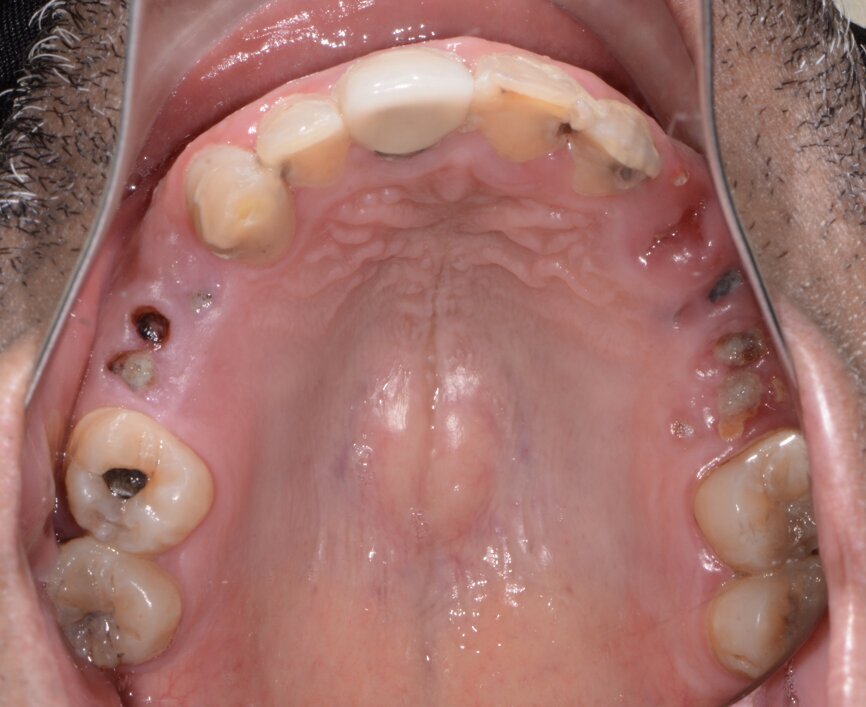

A patient presented to my practice for a consultation wanting to restore his dentition to proper form and function (Fig. 1). He complained of generalised discomfort due to the gross caries and periodontal disease that was readily apparent (Figs. 2 & 3). There were several teeth in both arches that had so much extensive decay that only the root tips were apparent upon clinical examination. Also, there was hyper-eruption in certain areas of his posterior dentition, as well as a deep impinging bite in the anterior.

Fig. 2: Pre-op maxillary occlusal view.